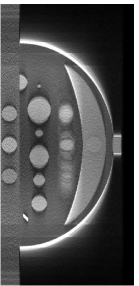

II Breast Phantom

A breast phantom was designed to provide a basis for algorithm comparison. It consists of objects with different geometric shapes to allow for analytic computation of the projection data. The overall shape of the compressed breast of 50 mm thickness is modeled by a truncated ellipsoid. Attenuation coefficients at a photon energy of 30 keV [10] were used for phantom materials simulating the fibroglandular, tumour and muscle tissues, as well as microcalcifications in the breast. In Fig. 1, we display the phantom images within 2D planes specified by (a) mm, by (b) mm, (c) mm, and (d) mm, respectively. As shown in Fig. 1a, the crescent-shaped region, representing the fibroglandular tissue region of the breast, is attached to a rectangular slab of higher attenuation, simulating the pectoralis muscle. It can be observed in Fig. 1 that numerous test objects of different sizes and contrast levels are embedded in the phantom for simulating mass lesions and microcalcifications. In particular, a row of three ellipsoids is embedded in the pectoralis muscle (see Fig. 1(b)), with equal in-plane diameters but varying flatness, thus allowing one to evaluate whether shapes of equal in-plane profile, but different in-depth profiles, can be resolved. Furthermore, six spheres of different diameters, ranging from 5 mm to 15 mm, are equally distributed in the fatty area of the breast (see Fig. 1(c)). It can also be observed in Fig. 1(d) that three pairs of stacked spheres of identical diameter mm are embedded in the breast region with different spacings of , , and , respectively, for these pairs. Finally, two clusters of small spheres of diameters 0.3 mm and 0.15 mm are included to model microcalcifications.